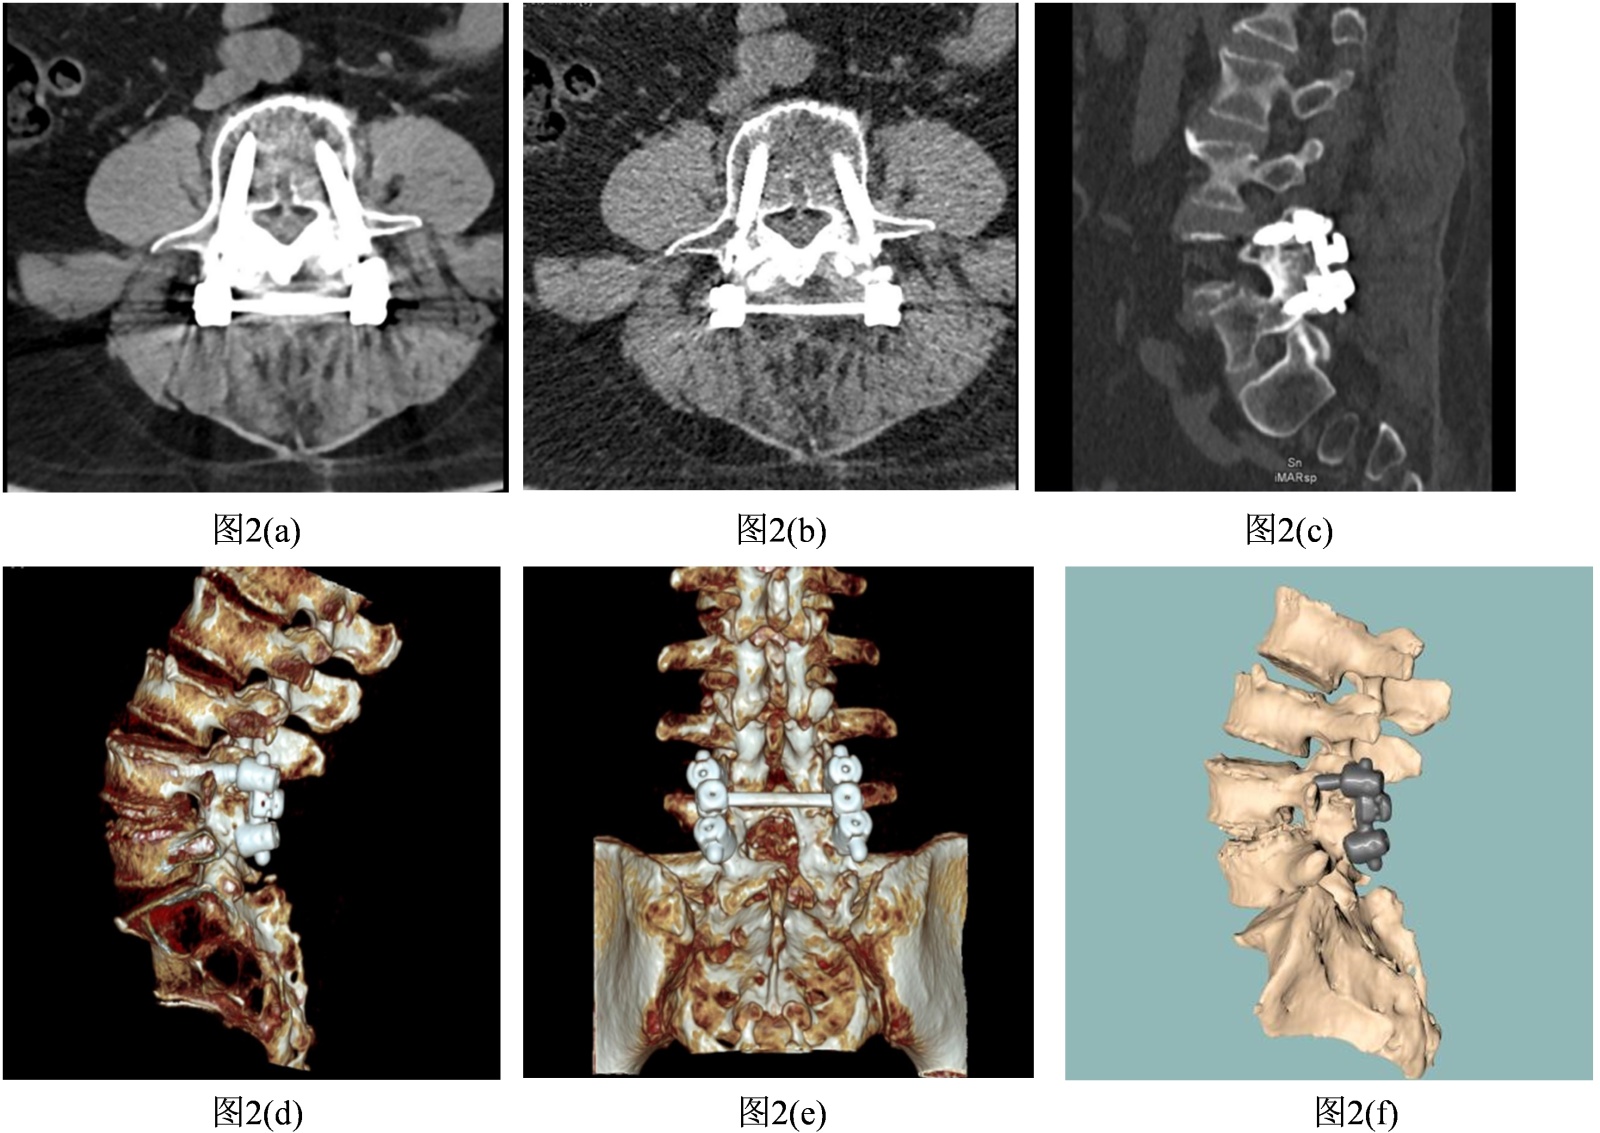

选取1例临床典型病例,采用“原始伪影图像→单一技术对比→多技术融合图像”的三段式展示,所有案例均来自本院临床病例,图像采集设备为西门子driver双能量CT,扫描见图2,扫描参数:管电压100/140 kvp双能量,管电流200 ma,层厚0.8 mm,螺距1.0。

Figure 2. Effect diagram of artifact removal after spinal internal fixation surgery using titanium alloy screws

2. 脊柱内固定术后(钛合金螺钉)伪影去除效果图

1. 原始含伪影图像(fbp),见“图2(a)”:轴位图像中,l4~l5钛合金螺钉周围可见轻微条状伪影(密度800~1000 hu),螺钉与椎体界面模糊,无法评估螺钉松动。Fbp重建,低原子序数金属伪影相对轻微但仍干扰关键结构判断。

2. 单一技术处理对比图,见“图2(b)”:(imar)伪影减轻50%,螺钉–骨界面清晰,但噪声略高(信噪比20 db);图2:(dect 120 kev):信噪比提升至24 db,但细节分辨率不足;图2:(三维迭代重建):空间分辨率达12 lp/cm,但伪影残留。单一技术可改善某一指标,但无法同时满足“低伪影 + 高分辨率 + 低噪声”。

3. 多技术融合图像,见“图2(c)~图2(f)”:采用100/140 kvp双能量 + dlr (骨骼模型) + 三维迭代重建 + vr组合方案,螺钉形态、椎体骨质及椎管清晰可辨,准确评估螺钉位置无松动,椎管无狭窄(vr图像直观展示内固定系统整体形态,便于医患沟通) [9]。融合技术适配低原子序数金属特点,双能量保证对比度,dlr平衡噪声与细节,三维迭代 + vr提升空间显示效果,兼顾诊断与沟通需求[8]